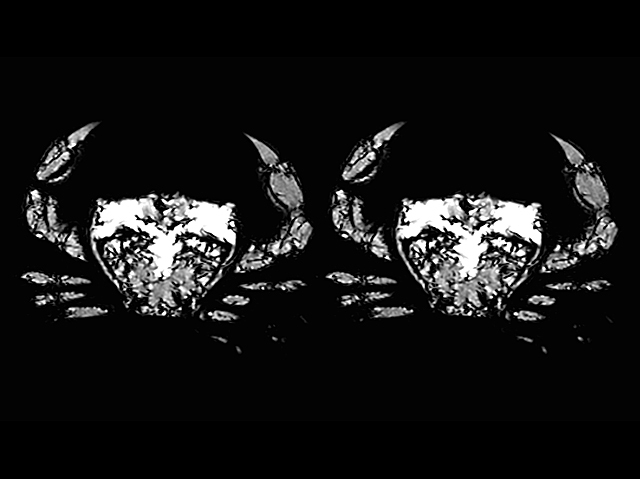

Rather than ending up on a dinner plate, this crab is demonstrating an important new piece of medical technology. It’s been put into a machine known as an MR Linac, which uses magnetic resonance imaging (MRI) to visualise the inside of a patient’s body (or crab’s body) in real time as well as delivering cancer-killing radiotherapy. This is particularly useful for treating cancers that move within the body, such as lung tumours. It’s also handy for spotting cancers that don’t show up easily with other imaging methods. The image on the left was taken using just the MRI scanner, while the one on the right was receiving radiotherapy at the same time. There’s no difference between them, proving that the radiation beams don’t affect the picture quality. Visualising tumours so clearly means that radiotherapy doses can be targeted more accurately, preventing damage to nearby healthy tissue and reducing side effects.